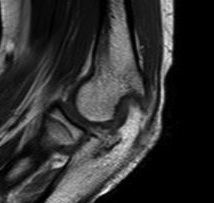

MRI

Useful in detecting early chondral damage

MRI chondral damage radiocapitella joint Chondral thinning anterior ulnohumeral joint

Chondral changes in the radiocapitellar and ulnohumeral joint